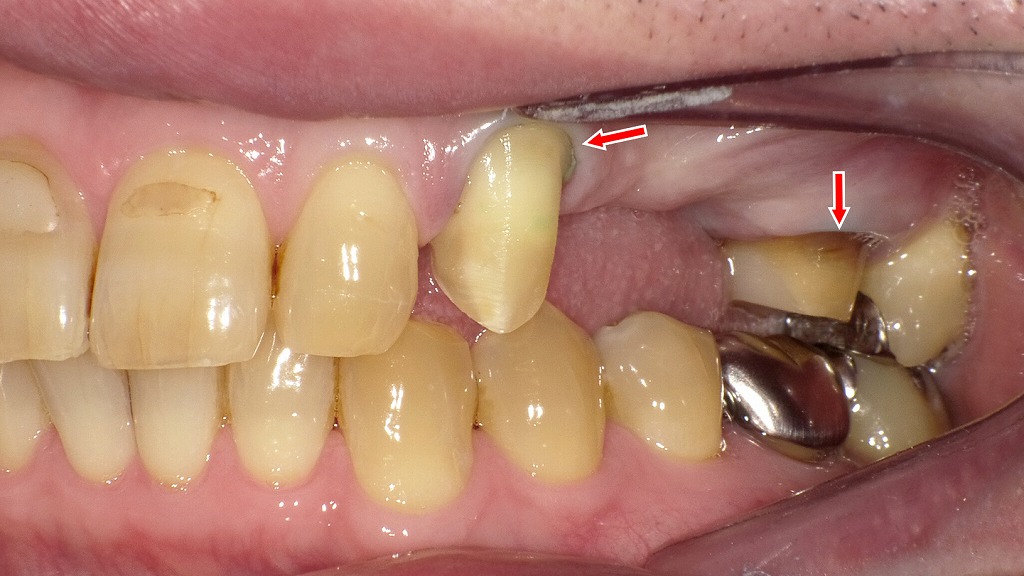

上顎左側犬歯(3番)から第1大臼歯(6番)にかけて、メタルボンドブリッジの支台歯形成後の状態を示しています。

矢印で示された部位には、印象採得(型取り)前の準備ができます。

🔹 上顎3番(犬歯)

- **生活歯(歯髄が残っている)**であり、支台歯形成が適切に行われています。

- 歯質は健全で、削合量は最小限。歯肉縁部には軽度の圧排糸が確認され、マージン部(形成境界線)が明瞭に見えます。

- 支台形態はクラウン用のテーパーが適正で、後方の6番と連結予定の支台として整えられています。

🔹 上顎6番(第1大臼歯)

- **ファイバーコア(グラスファイバー強化樹脂製コア)**が築造されています。

- 歯冠部は滑沢に形成され、金属支台ではなく光透過性のあるファイバーコア材が使用されていることから、審美性・接着性を考慮した設計であると分かります。

- 歯肉縁には圧排糸が挿入されており、印象時にマージンを正確に再現できるよう準備されています。

🔹 欠損部位(上顎4番・5番相当)

- 3番と6番の間には歯の欠損があり、ブリッジのポンティック部が設置される予定です。

- 歯槽堤の吸収は軽度で、粘膜状態は健康的。ポンティック設計(リッジラップまたはモディファイドリッジラップ)が適応可能な状態。